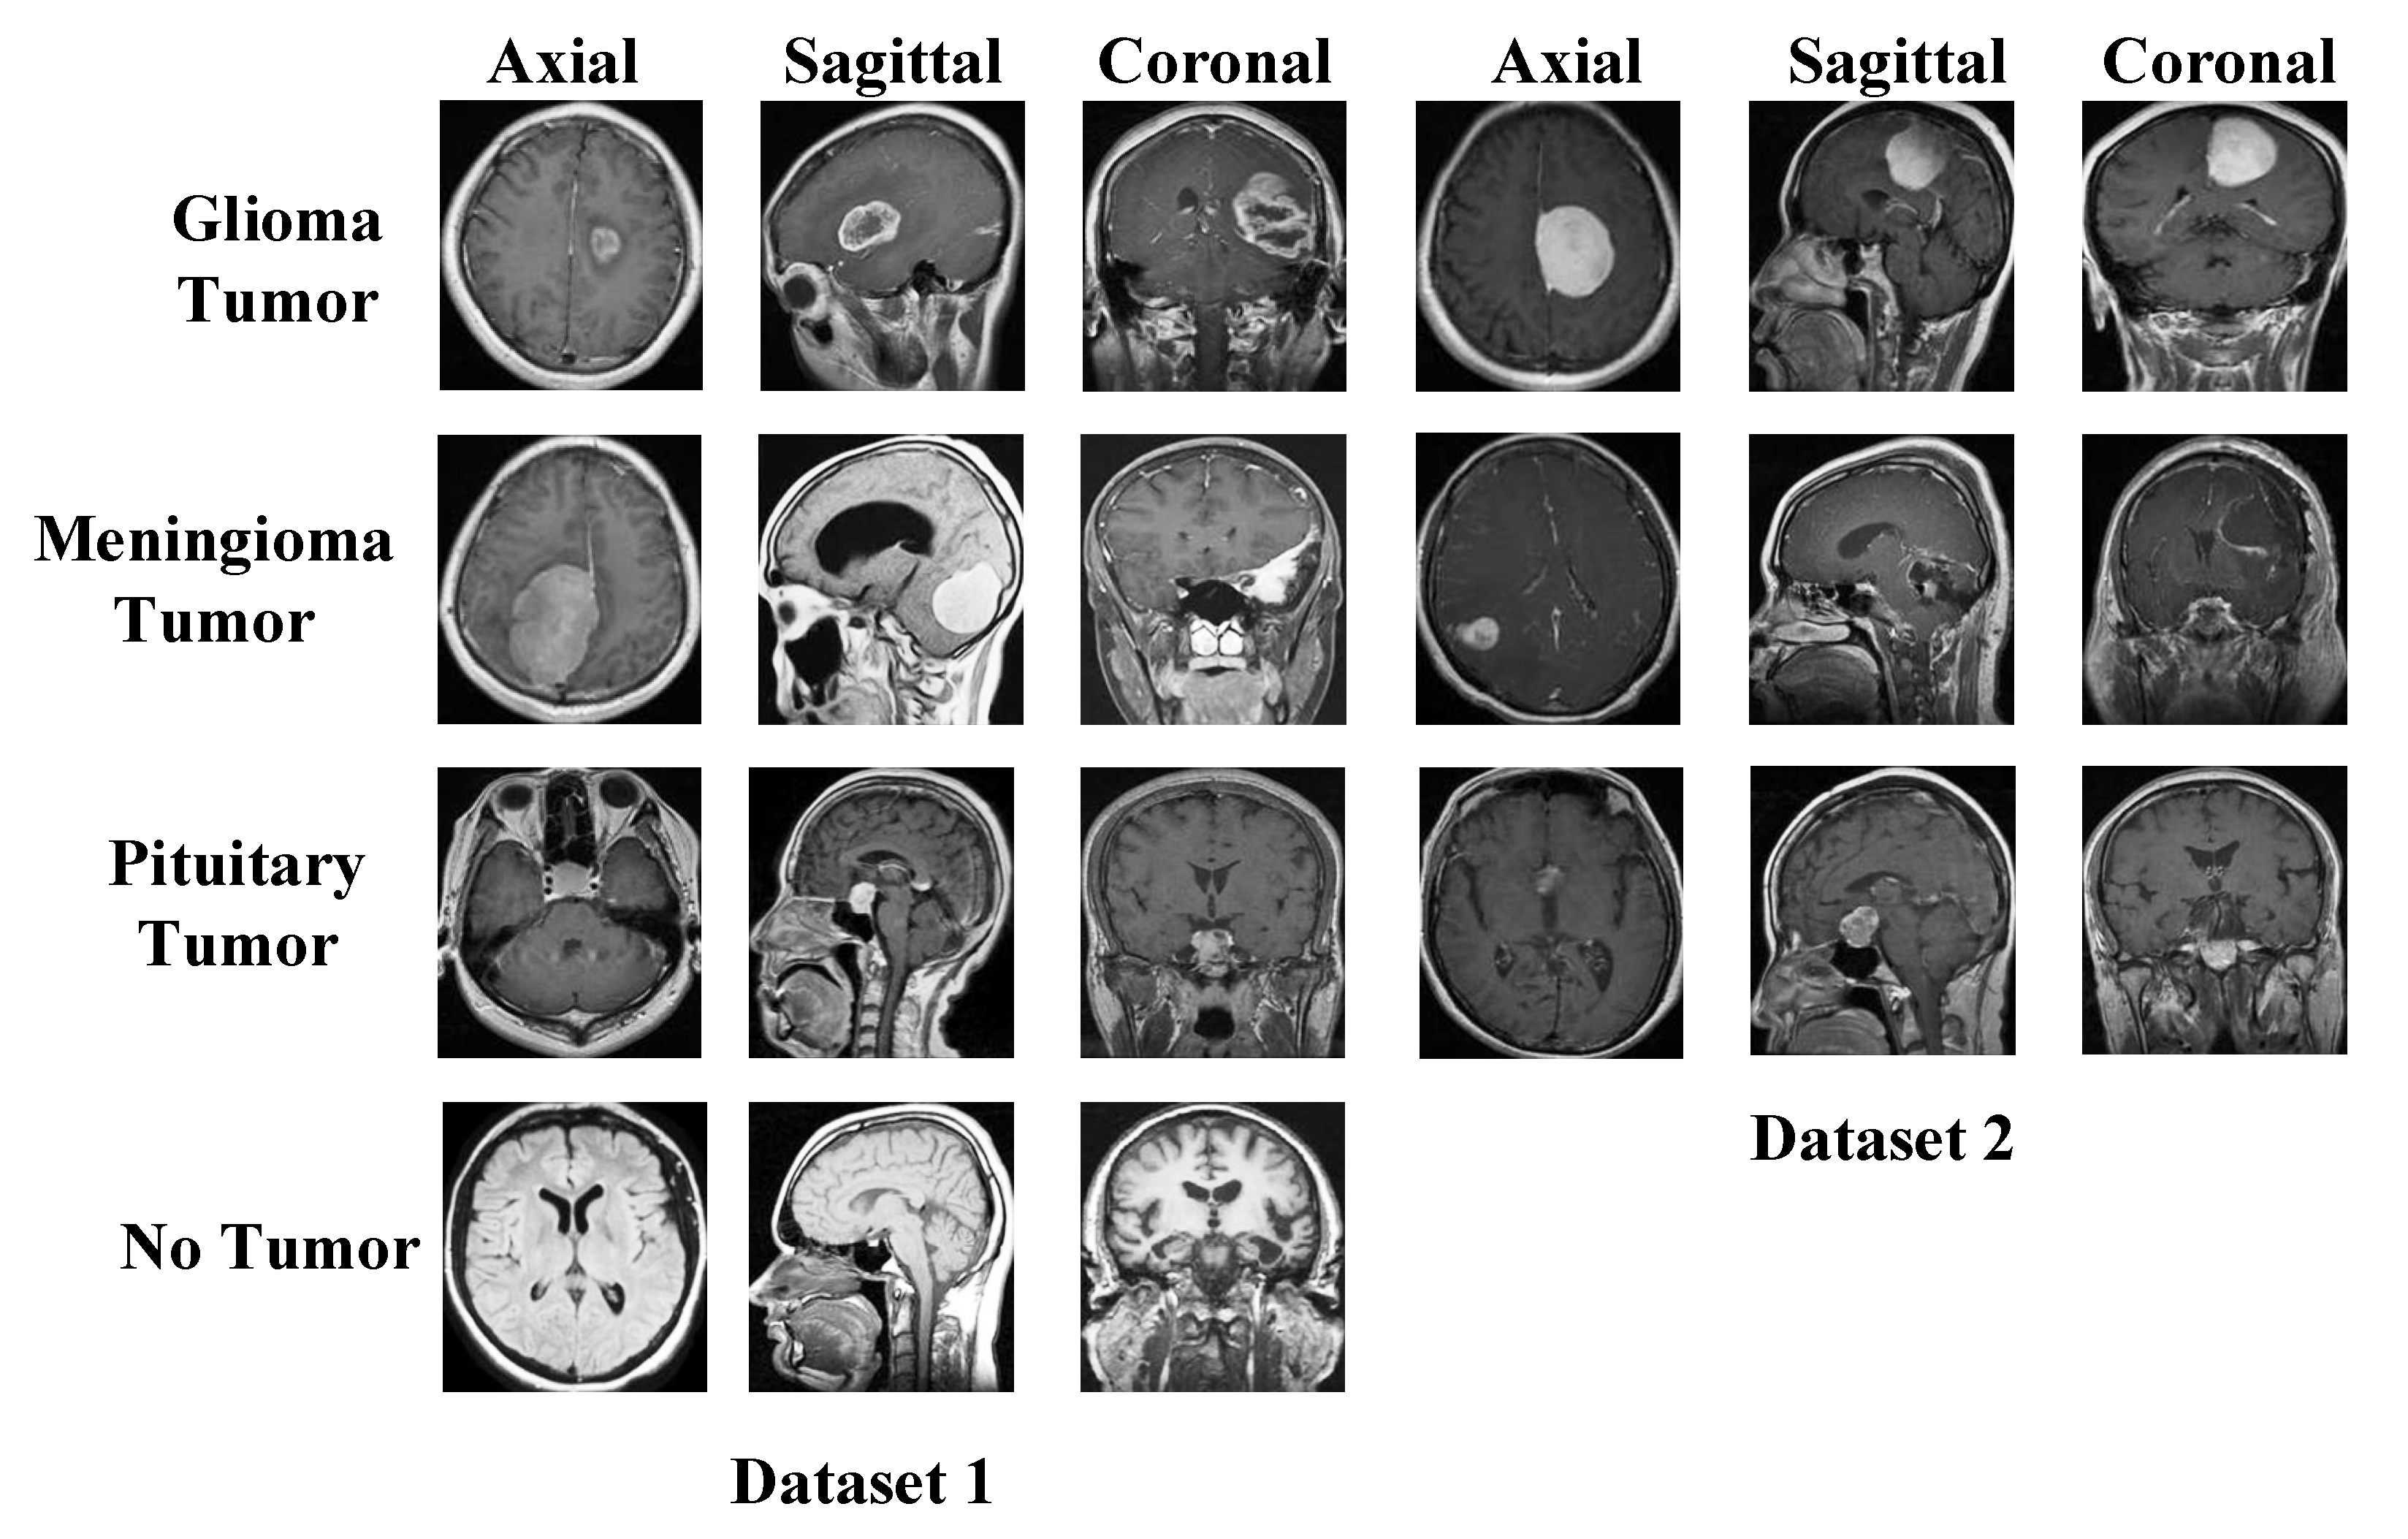

- To show the superiority of our proposal, we have used two public brain tumor image datasets. These datasets contain four and three categories. We obtained a pre-trained network by using a dataset with four classes and DenseNet201. Using this pretrained DenseNet201, preprocessing and feature extraction layers of our model have been created. In this respect, a deep learning-based cognitive model has been created. Moreover, our model attained superior classification performances than other state-of-art models.

2.1. Dataset I

2.2. Dataset II